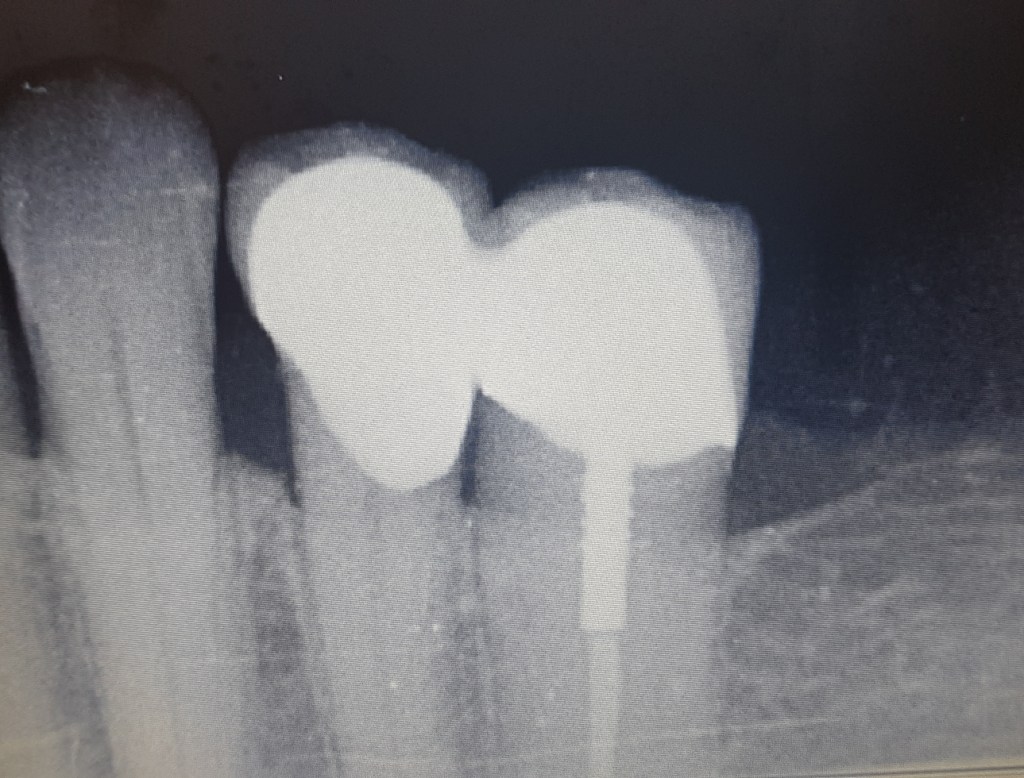

A gyökércsatornába beragasztott csap lehetőséget teremtett a fog koronázására, ám statikai okból a szomszédos fogra is korona készült.

Nem csak foghiány, azaz fogak pótlása esetén érdemes lehet tehát fogakat egymással összekötni(sínezni).

Meggyengült, ám megmentésre még érdemes fogak így ellenállóbbak a rágóerő okozta stressznek így hosszabb élettartamot és jobb funkcionálást válhatunk tőlük.